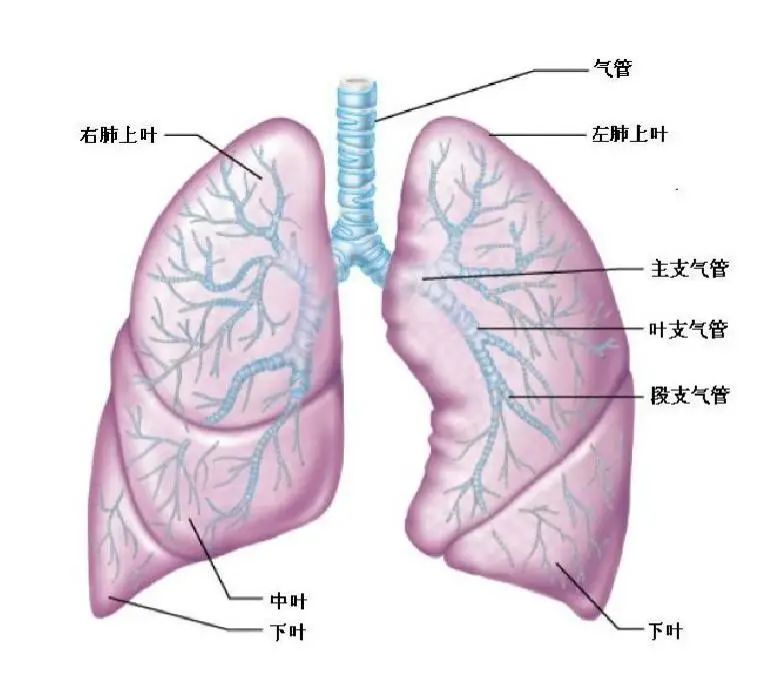

没想到我这么大岁数,切掉一个肺叶的十年后,再次做这么复杂的手术还这么顺利。 D大爷今年72岁,10年前曾行左肺上叶切除+淋巴结清扫术,手术标本病理为腺癌,术后给予了四次化疗。当时的胸部CT即可见右肺上叶小结节影,术后定期复查,病灶缓慢增大,一度略有缩小,此后再次逐渐增大。结合患者一直随访的影像学资料,杨如松院长考虑为右上肺新发恶性肿瘤。 2015年胸部CT 2020年胸部CT 虽然患者及其家属手术的意愿非常强烈,但此手术难度较高,原因在于: 1.患者年龄较高,手术风险大。 2.患者10 年前肺癌手术切除左边肺的一半,肺功能丧失较多。 3.病灶在右上肺的深部,切除有一定的难度。 为了保证患者术后的生活质量,我们不能够做肺的楔形切除这样的简单肺手术,而需要行肺段的切除。 EDDA重建提示病灶位置深 如果放在以前该患者就只能做做放化疗等保守治疗了。幸亏南京胸科医院目前引进了各种国内乃至国际上的先进技术。 如EDDA术前三D成像技术;只有单一3cm长切口的单孔胸腔镜技术;近红外荧光镜肺段、亚肺段精准定位技术等。 有了这些技术,杨如松院长心中有了底气。杨院长根据病人的情况设计手术方案,尽量减轻手术创伤,让接受第二次肺部复杂手术的高龄病人能够耐受,并且在术后能够顺利恢复。 根据术前EDDA三维重建,患者进行了单孔荧光胸腔镜S1a+2a切除术,术中先用ICG反染法确定段间面,再用膨胀萎陷法印证段间面,这保证了手术切除的精准性。 患者术中快速病理为贴壁型腺癌,这也印证了杨如松院长术前对患者肺结节良恶性的判断。 术后5天,D大爷非常顺利的出院了。出院前开心的窦大爷连声感谢杨如松院长:没想到我这么大岁数,切掉一个肺叶的十年后,再次做这么复杂的手术还这么顺利,谢谢、谢谢! 基本情况